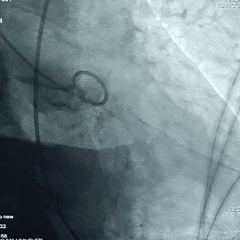

18mm球囊预扩张

瓣膜初始定位

瓣膜展开至工作位

瓣膜工作位评估

瓣膜工作位多角度评估

瓣膜稳定脱钩